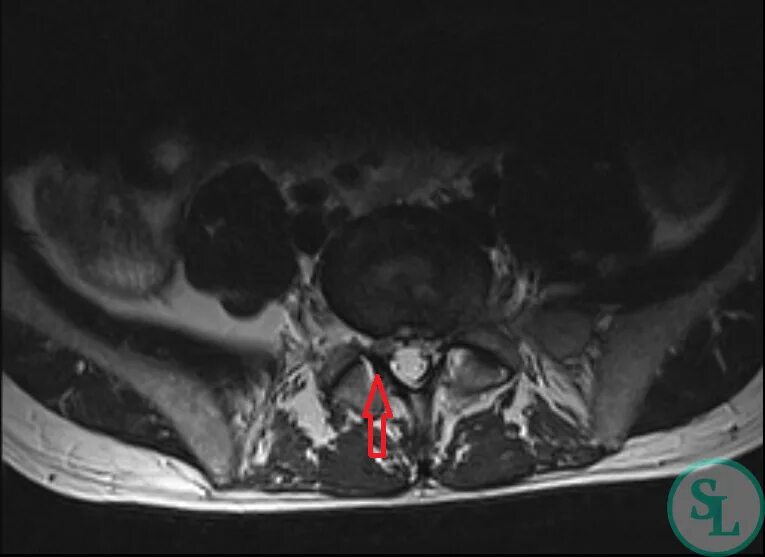

Грыжа экструзия диска l5 s1